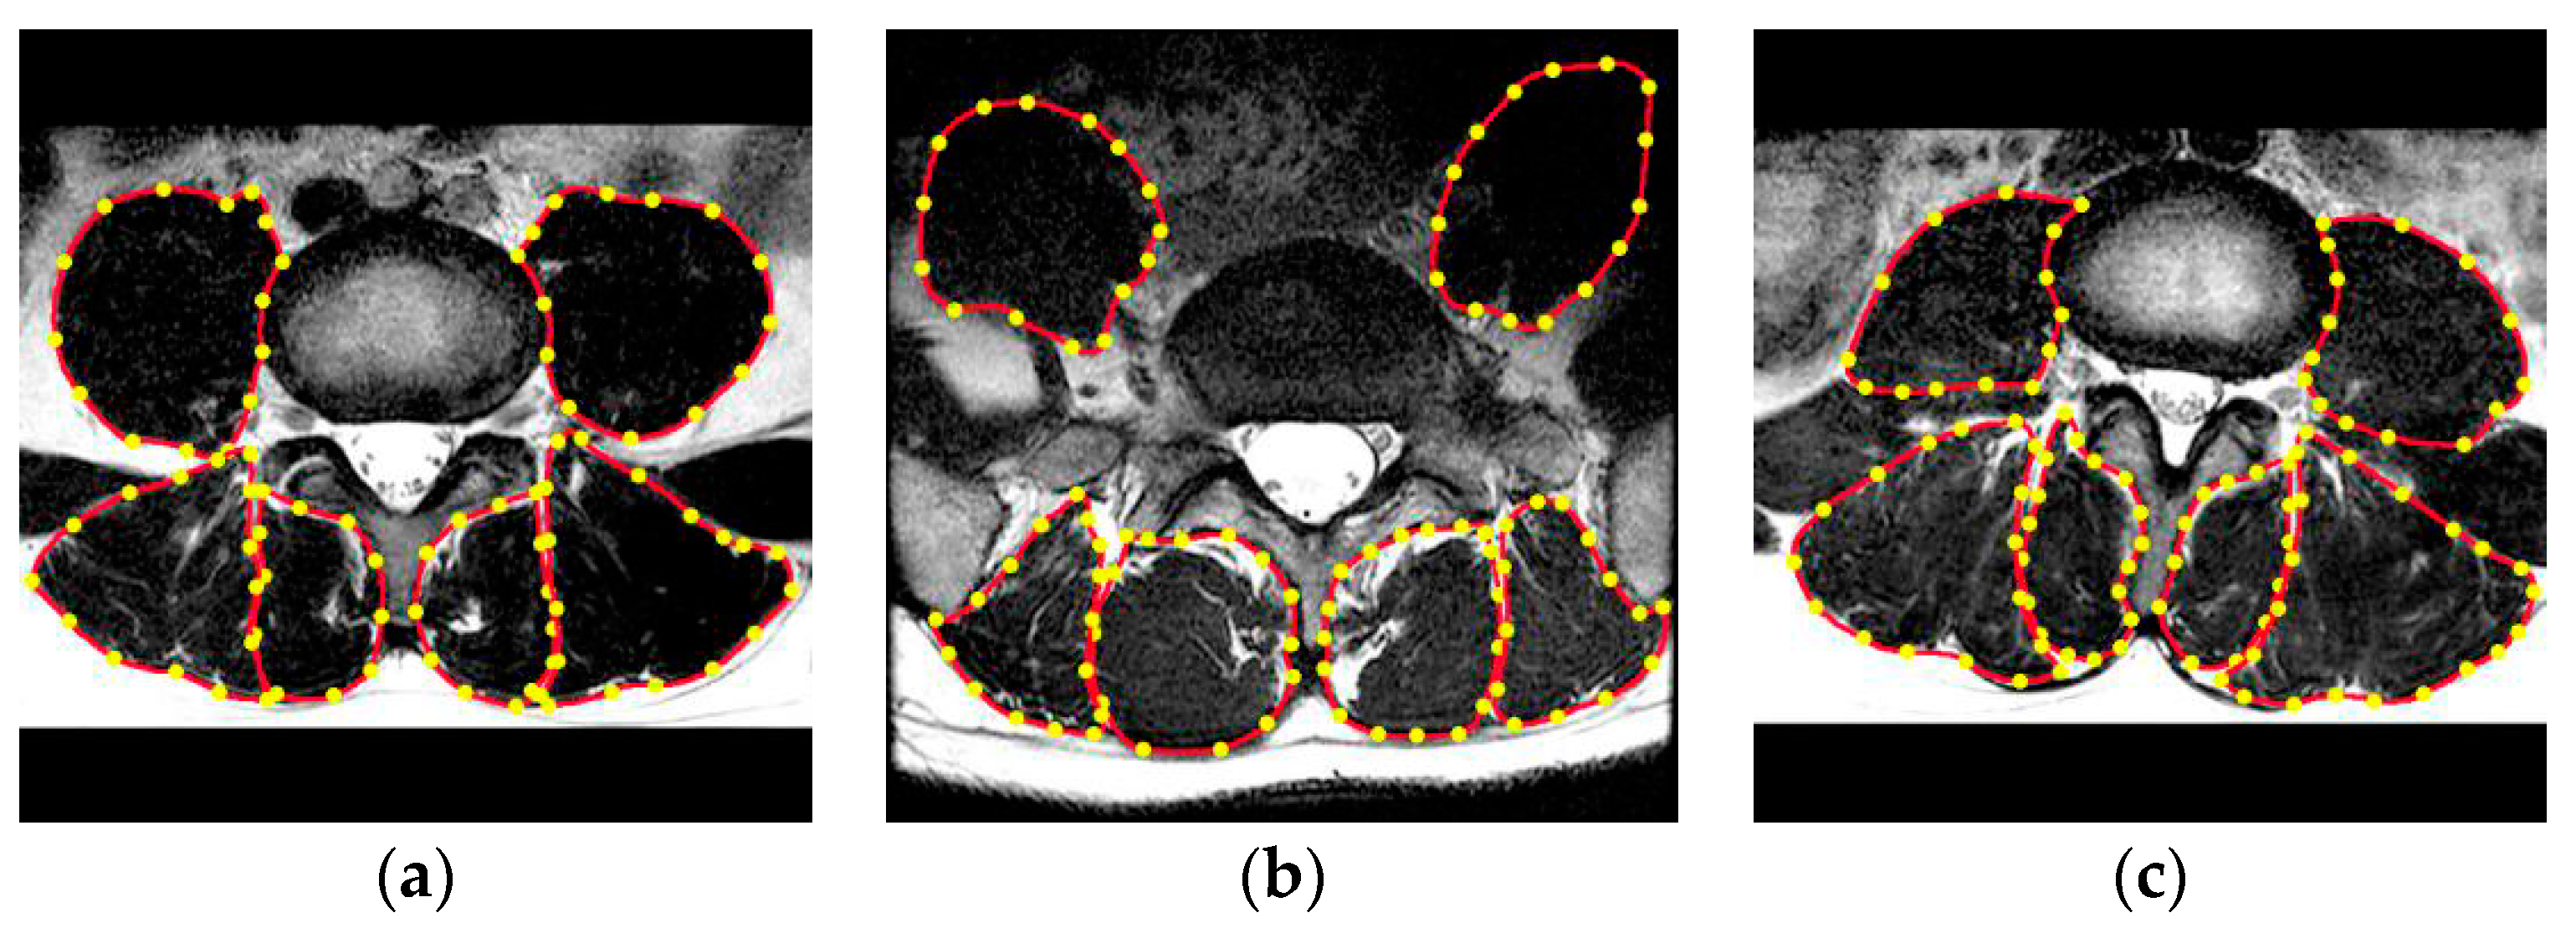

3.1. Dataset

3.4. Modules Analysis by Intra-Comparison

3.5. Comparison with other State-of-the-Art Methods